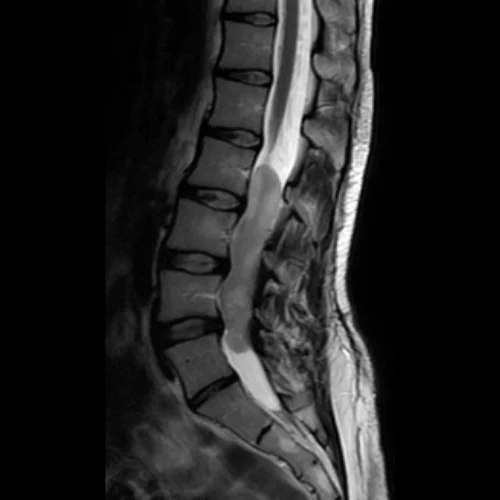

Peripheral Nerve Tumors

Homepage Peripheral Nerve Tumors